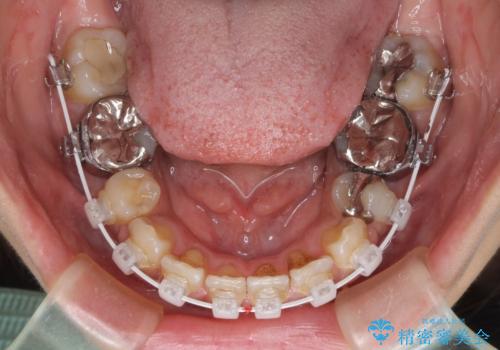

デコボコと口元の突出感 ハーフリンガルでの抜歯矯正

- 前歯のデコボコと上顎の前突感による口の閉じにくさを気にして来院された患者様です。

目立たない装置を希望されたので、上顎が裏側装置のハーフリンガルを選択し、上下左右の小臼歯(計4歯)を抜歯して矯正治療を行うこととしました。